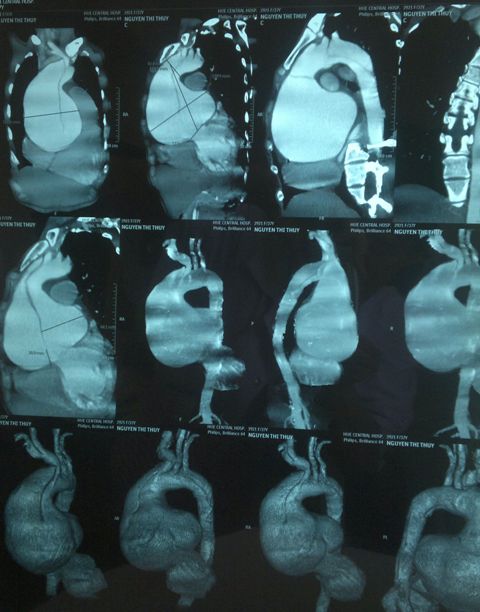

Phình động mạch chủ lên

Phim chụp CT 64 thấy túi phình rất lớn